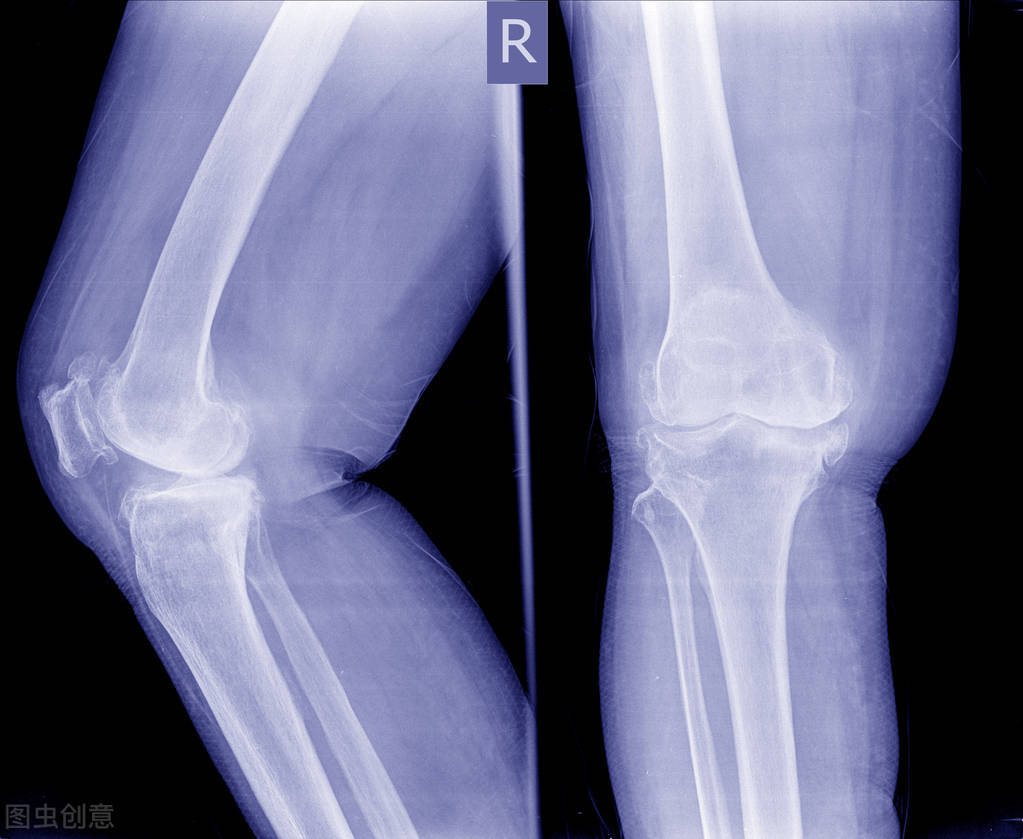

膝关节术后须尽早进行系统规范的康复治疗

膝关节手术是治疗各种疾病导致膝关节毁损病变的重要手段,但只把治疗成功完全寄托在手术上,而不进行术后康复训练,则不能达到理想的疗效。膝关节术后的康复治疗已成为手术不可或缺的一部分。通过术后早期系统、科学规范的康复治疗,可以达到预防术后并发症、改善膝关节活动范围和恢复步行能力的目的,最终使手术疗效达到很高的水平。否则,膝关节会因为长期制动而导致功能受限,无法自如弯曲伸直下蹲,将会严重影响患者的日常生活。